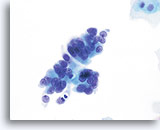

Adenocarcinoma in situ

A strip of endocervical cells exhibiting pseudostratification and finely vacuolated cytoplasm with indistinct cytoplasmic borders. Architecture is disrupted although cells are still attempting to maintain a glandular configuration. Note increased N/C ratio and the variable presence of nucleoli. Biopsy – AIS – 60x